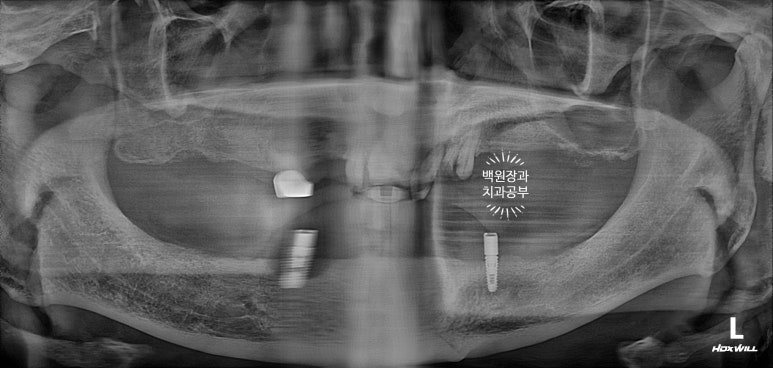

저희 병원에 처음 오셨을 때 치과용 파노라마 엑스레이 사진이에요.

치아가 거의 없으셨어요... 뿌리만 남은 위턱 치아들은 모두 제거하기로 하였고....

이제 임플란트주위염 (peri-implantitis)로 사용하기 어렵게 된 임플란트를 포함하여 2개 모두 제거하기로 했습니다.

그리고 왼쪽 사진을 보시면, 회색의 무언가가 보이실텐데...

잇몸뼈 안에 있어야할 임플란트가 주변의 뼈가 녹아 없어지면서 드러나 있는 상태였어요.

위턱을 보시면 정말로 뿌리만 있는 치아를 보실 수 있어요.

다만, 남은 잇몸뼈들은 상대적으로 건전하여 틀니를 하기에는 무리가 없어 보였습니다.

아래는 임플란트 2개를 이용한 임플란트 틀니 (=오버덴쳐)를 사용중이셨는데요,

왼쪽 임플란트는 이미 잇몸 밖으로 임플란트의 일부가 드러나 있었어요.

임플란트 주위염이라고 부르는데요~ 상태가 심각하여 제거해야하는 수준이었습니다.

비교적 오른쪽 임플란트는 낫군요..